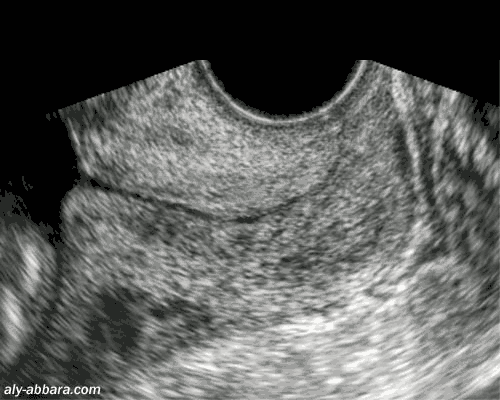

Coupe sagittale passant par le col utérin à 22 semaines d'aménorrhée

Il s'agit d'un col de longueur et d'aspect normaux

Incompétence cervico-isthmique